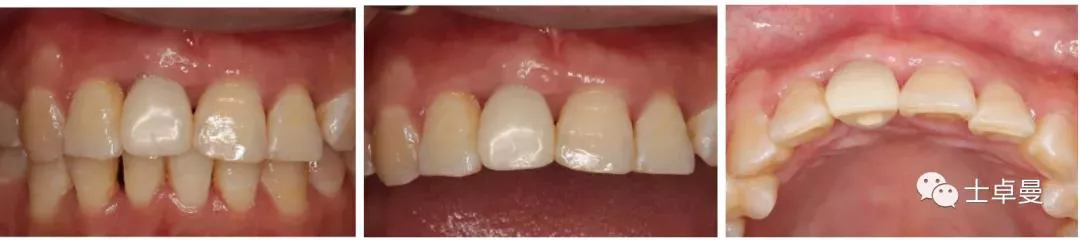

·      ▷ 就诊时检查口内检查

·      11伸长,牙龈呈紫红色,BOP(+),松(Ⅲ);

·      12松(Ⅰ-Ⅱ),21松(Ⅰ-Ⅱ),22松(Ⅱ);

·      牙龈未见明显炎症,余留牙未见异常;

·      咬合正常,低位笑线,中厚龈生物型;

·      牙周系统治疗中,全口卫生状况可,无明显结石,可见少量软垢。

▷ 种植牙前检查(牙周系统治疗3个月后)口内检查

·      11缺失,拔牙创愈合良好,12松(Ⅰ-Ⅱ),21松(Ⅰ-Ⅱ),22松(Ⅱ),余留牙未见异常;

·      全口卫生状况良好,无牙结石。